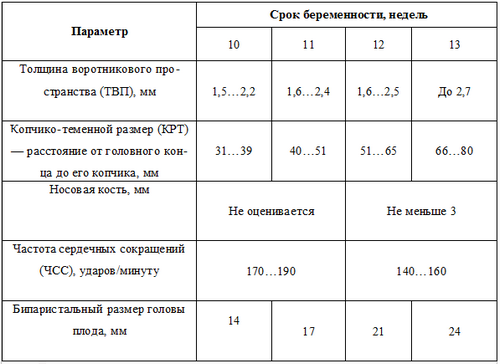

Як протікає процес ультразвукового дослідження? Лікар знімає з ембріона (плода) ряд вимірів. Є спеціальні таблиці, за допомогою яких можна порівняти ступінь розвитку внутрішніх органів майбутнього малюка з еталонними значеннями. Зіставляючи ці цифри, доктор робить висновки про життєздатність зародка і відсутності у нього вроджених патологій. Перше УЗД може бути:

- Робляться виміри, які повинні лежати в наступних межах:

Після процедури вам видадуть протокол з результатами УЗД. Таблиця наведена нижче, допоможе вам при розшифровці УЗД. Наведено середні цифри (при 50 процентиль).